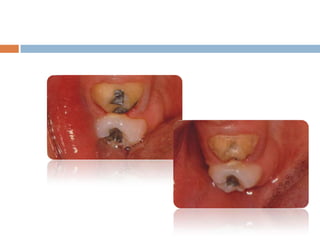

This document discusses common problems that can occur with crowns and bridges (C&B) and their solutions. It covers issues with impressions, frameworks, cementation and clinical/laboratory techniques. Some key points: - Impression problems like voids, tears or lack of detail can result in poor fitting restorations. Solutions include improving retraction, moisture control, and using appropriate materials and techniques. - Framework issues like porcelain fractures, solder joint failures or distortion can cause restorations to fail. Rounding internal line angles, ensuring adequate porcelain thickness/support, and preventing flaws can help. - Changes in abutment teeth over time from issues like periodontal disease, caries or